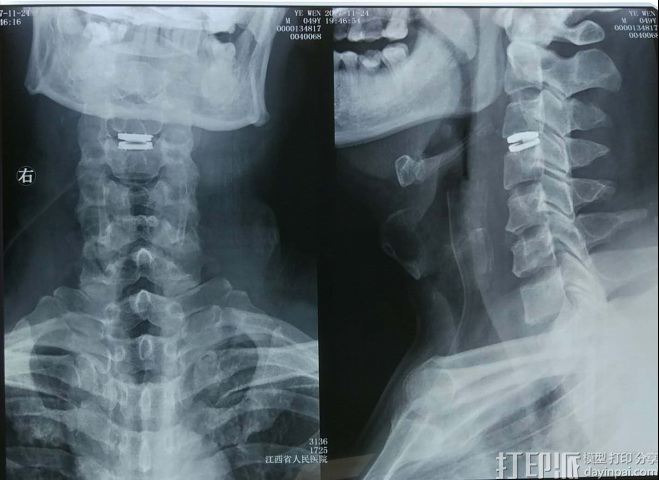

看到漂亮的术后X光片,体会到麻醉醒后立竿见影的手术效果,叶先生兴奋不已。就在进手术室前,电视台记者采访他时,他的左手还不能用力㧓握,右手更是无法握拢,而术后一觉醒来,他两只手都可以握住甚至抓牢主刀医师董谢平的手了;术前的蹒跚步态也变得稳健了。晚上来看望他的家人走到近前发现站在走廊上与医生交谈的病人竞然是他们的亲人时,都惊喜得合不扰嘴来。

这次手术的成功不仅给叶先生带来了新生与幸福,对实施手术的江西省人民医院来说,也有特殊的意义。明天就是江西省人民医院建院120周年庆典大会,据悉,本次手术既是江西省自主开展的第一例人工椎间盘置换手术,也是新一代人工颈椎间盘BAGUERA c今年11月16日在珠海全国骨科年会既COA大会上正式宣布进入中国后的首例手术,标志着江西省人民医院骨科学科建设迈上了一个新台阶,也是骨二科为120周年院庆献上的又一份礼物。

江西省人民医院骨二科主任董谢平通过学术活动,欣喜地发现了这款新产品,并敏锐地捕捉到上述不足。为将新一代人工颈椎间盘的优势发挥到极致,他利用丰富的骨科临床与3D打印经验,设计并3D打印了一套人工椎间盘安装导板,还按1:1比例打印出颈椎动态模型,据此挑选了最合适型号的假体,并精准实施了人工椎间盘的置换手术。